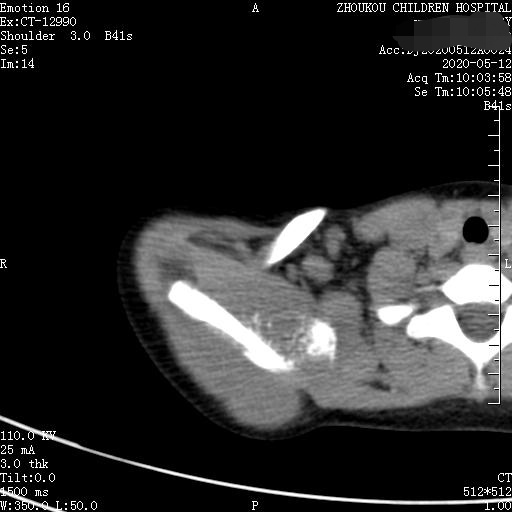

通过CT平扫发现:右侧肩胛骨骨质密度不均,骨质内可见“虫食样”低密度影,骨质边缘可见多发放射状骨针,呈“日光射线征”。周围软组织明显肿胀,肌间隙模糊。CT检查意见:考虑:右肩胛骨占位,骨肉瘤可能,不除外其它恶性肿瘤病变,请结合临床及相关检查注意复查。 影像鉴别诊断:骨肉瘤是指起源于骨间叶组织,遗留形成骨细胞直接形成骨样组织为特征的恶性肿瘤,是比较常见的骨恶性肿瘤,好发于十到二十岁青少年,骨肉瘤常见于管状骨,股骨远端胫骨近端最多见,表现为疼痛局部肿胀运动障碍,实验室检查都有碱性磷酸酶升高。

二、根据骨质破坏和肿瘤骨的多少,骨肉瘤可以分为三型,液化型以肿瘤新生骨为主,溶骨型是以骨质破坏为主,混合型新生骨的形成和骨质破坏并存,x线表现是不规则的骨质破坏伴浸润,可见日光样和放射状骨膜反应,骨膜新生骨在破坏可形成考特曼三角,骨内可见云状、絮状、针状、放射状肿瘤骨伴软组织肿块而形成。